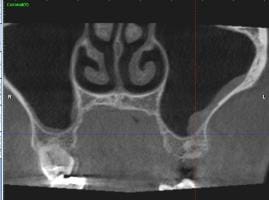

Esta semana me hicieron un tac, porque en la orto y en la radiografía periapical no salía nada. Le adjunto imágenes del mismo, y le agradecería enormemente su opinión.